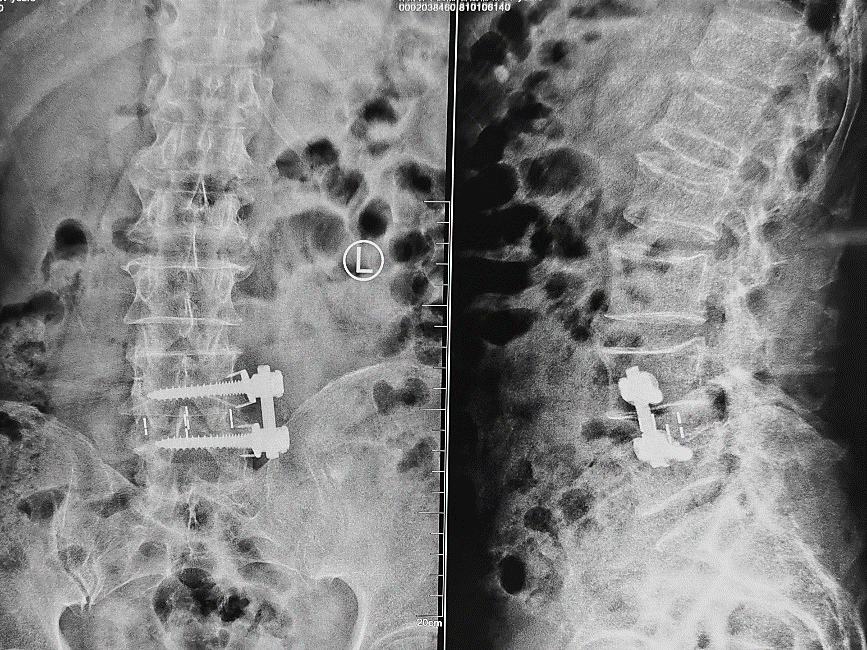

第二例患者男性,67岁,患者因“腰痛并右下肢放射痛1年余,加重1月”入院,发病以来反复保守治疗,未好转,1月前症状加重,间歇性跛行,行走100米后因疼痛无法继续行走。入院后经术前讨论、评估,制定治疗方案,行OLIF手术。次日患者下地活动,下肢症状消失,疗效满意。

术后复查

第三例51岁女性患者,因“右下肢放射性疼痛、麻木1年,加重1月余”入院,发病以来反复多次保守治疗无效。入院后经术前讨论、评估,制定治疗方案,行OLIF手术,该病例采用后路经皮椎弓根螺钉内固定。次日患者下地活动,下肢症状消失,疗效满意。

术前影像